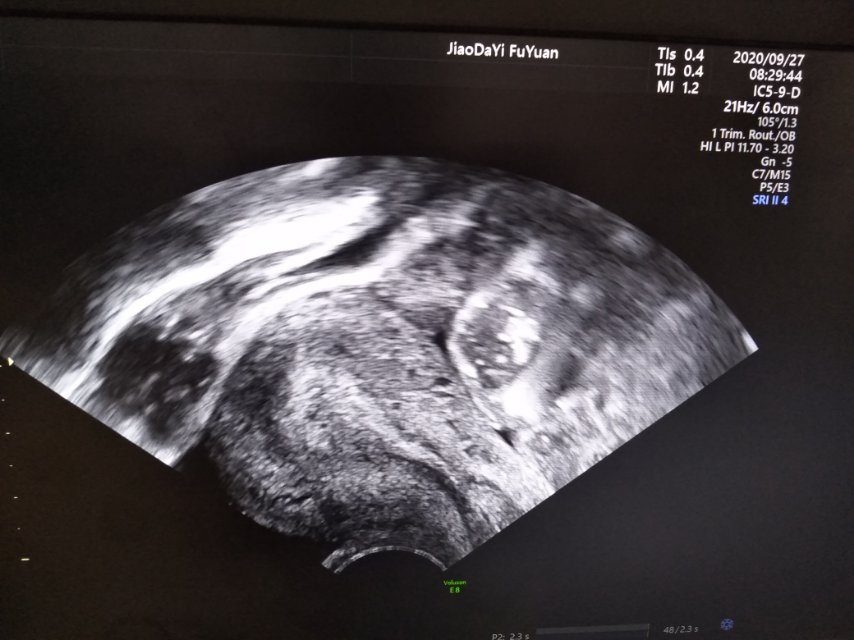

试管婴儿移植已经进周但有内膜分离的情况医生怀